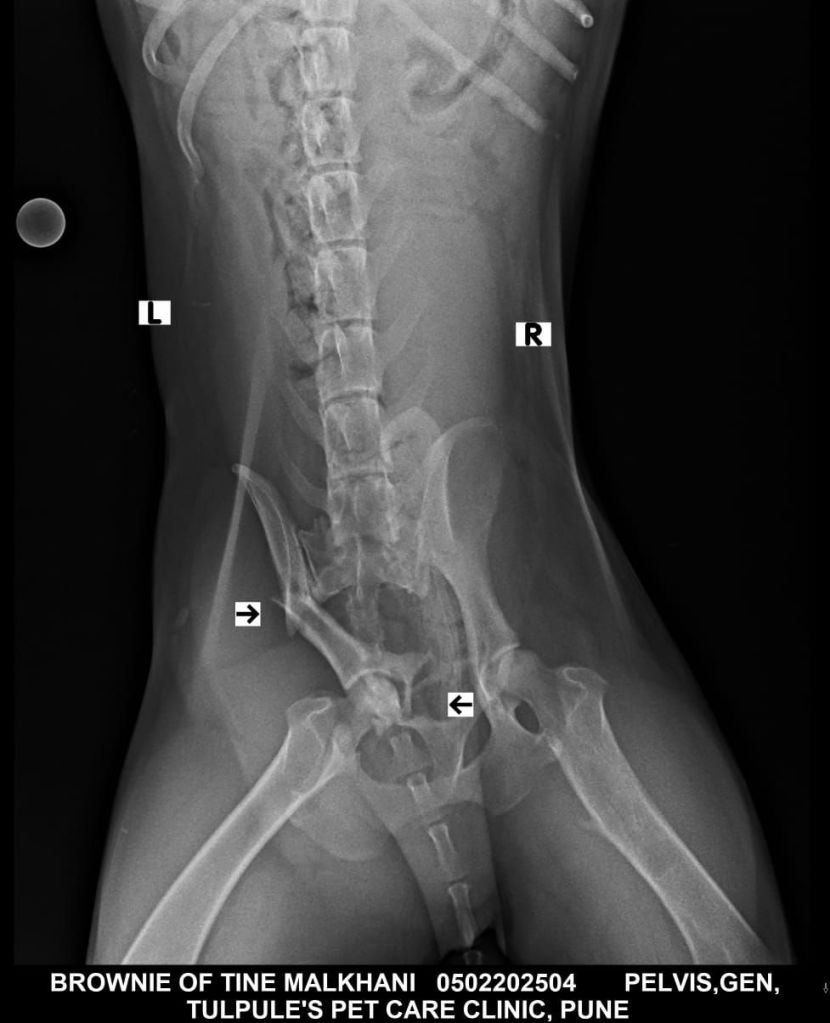

Got him checked and x-rays taken yesterday, his pelvic bone has broken in three places. It is not repairable 💔.. but the only hope is that he is able to stand on the other three legs.

So all we got to do is now let him rest for about 3-4 weeks with meds and supplements and pray hard that the bones fuse. If not , we will have to amputate that leg . He’s an old boy .. pls send him lots of love and prayers..